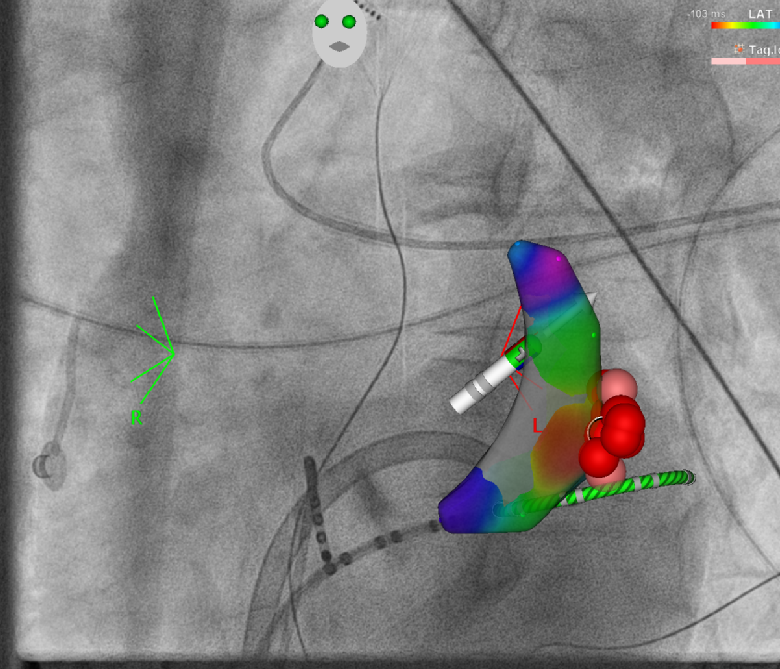

Im Rahmen spezieller elektrischer Herzkatheteruntersuchungen können wir die Reizleitungseigenschaften des Herzens untersuchen - hierzu werden über die Leiste elektrische Herzkatheter am Herzen positioniert und über Provokationsmanöver die Herzströme vermessen. Auftretende Rhythmusstörungen können unter Verwendung eines hochmodernen 3D-Navigationssystems mit Röntgen-Bildfusion genau kartiert werden, und können prinzipiell auch Strahlen- und Kontrastmittelfrei erfolgen. In gleicher Sitzung kann dann auch die Verödung der Herzrhythmusstörung erfolgen.

3D Navigation einer VES Extrasystolie

Links ein Echokardiogramm eines Herzens, rechts eine Substrat-Karte mit farbiger Visualisierung und Markierungen.